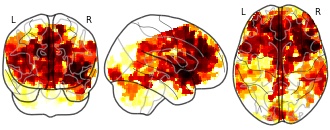

EmailClick to copy linkLink copied Cite(2018). Sliding-window analysis tracks fluctuations in amygdala functional connectivity associated with physiological arousal and vigilance during fear conditioning: PPI tfce corrp [Dataset]. http://identifiers.org/neurovault.image:43175niftiAvailable download formatsUnique identifierhttps://identifiers.org/neurovault.image:43175Dataset updatedJun 30, 2018License

Cite(2018). Sliding-window analysis tracks fluctuations in amygdala functional connectivity associated with physiological arousal and vigilance during fear conditioning: PPI tfce corrp [Dataset]. http://identifiers.org/neurovault.image:43175niftiAvailable download formatsUnique identifierhttps://identifiers.org/neurovault.image:43175Dataset updatedJun 30, 2018LicenseCC0 1.0 Universal Public Domain Dedicationhttps://creativecommons.org/publicdomain/zero/1.0/

License information was derived automaticallyDescriptionThis is an unthresholded TFCE map that was corrected for multiple comparisons (corrp). To visualize the results reported in the manuscript, threshold the map at 0.95, which corresponds to a corrected p value at 0.05.

Collection description

We evaluated whether sliding-window analysis can reveal functionally relevant brain network dynamics during a well-established fear conditioning paradigm. To this end, we tested if fMRI fluctuations in amygdala functional connectivity (FC) can be related to task-induced changes in physiological arousal and vigilance, as reflected in the skin conductance level (SCL). Thirty-two healthy individuals participated in the study. For the sliding-window analysis we used windows that were shifted by one volume at a time. Amygdala FC was calculated for each of these windows. Simultaneously acquired SCL time series were averaged over time frames that corresponded to the sliding-window FC analysis, which were subsequently associated with the whole-brain seed-based amygdala sliding-window FC using the GLM. Surrogate time series were generated to test whether connectivity dynamics could have occurred by chance. In addition, results were contrasted against static amygdala FC and sliding-window FC of the primary visual cortex, which was chosen as a control seed, while a physio-physiological interaction (PPI) was performed as cross-validation. During periods of increased SCL, the left amygdala became more strongly coupled with the bilateral insula and medial prefrontal cortex, core areas of the salience network. The sliding-window analysis yielded a connectivity pattern that was unlikely to have occurred by chance, was spatially distinct from static amygdala FC and from sliding-window FC of the primary visual cortex, but was highly comparable to that of the PPI analysis. We conclude that sliding-window analysis can reveal functionally relevant fluctuations in connectivity in the context of an externally cued task.

Subject species

homo sapiens

Modality

fMRI-BOLD

Analysis level

group

Cognitive paradigm (task)

pavlovian conditioning task

Map type

P